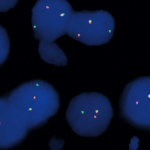

Quick Order Quick Order Name Email Address Company Address Catalog Number Quantity Message 14 + 5 = Submit Category Blocking Reagents Both Counterstain Country International US Detection Kit Detection Kit Detection kit 1-Step Polymer Kit Detection Kits - IHC 1-Step Polymer HRP Kits IHC AP Detection Kit IHC HRP Detection Kit IHC Mouse on Mouse 1-step Poly HRP kit New & Improved 1-Step Polymer HRP Kit IHC New & Improved Polymer HRP Kits IHC Polymer HRP Kits IHC Rapid Polymer HRP Kits IHC Double Staining eFISH Detection Kits ISH-Detection Kits Multiplex Detection Kits New & Improved Detection Kits Polymer HRP Kits IHC eFISH Enzymes for Tissue Processing Enzymes for Tissue Processing i6000 and Manual Instruments ISH Probes ISH-Detection Systems Links / Labels items-Manual Microscope Microchamber Slides & Coverslips for Xmatrx Microscope Slides & Accesories for i6000 and Manual Microscope Slides & Accessories Microscope Slides & Accessories miRNA Probes Primary Antibodies A Antibody Cocktail B C D E F G H I J K L M N O P R S T U V W Y Z Reagents Antigen Retrieval Solutions Blocking Reagents Blocking Reagents Buffers and Diluents Buffers eFSH Buffers ISH Buffers Counter Stains Detection Kit Dewaxing & Rehydration Reagents Diagnostic Antigen Retrieval Solutions eFISH Antigen Retrieval Solutions ISH Blocking Reagents ISH Enzymes Mounting Media eFISH Mount Media Nucleic Acid Retrieval Substrates & Chromogens ISH DAB replacements Slide Labels Vials Immunohistochemistry In situ Hybridization eFISH eFISH Probes eFISH Visualization Kits eFISH Visualization Kit Cyto eFISH Visualization Kit Histo Visualization Kit Ancillaries & Consumables Consumable Kits IHC Consumable Kits ISH Consumable Kits Counterstain and Mounting Media Counterstain Mounting PAP Pen Pipette Tips Reagent Vials & Accessories Reagent Vials & Accessories for i6000TM Diagnostics Reagent Vials & Accessories for Open system Automation Reagent Vials & Accessories for Xmatrx Elite Reagnet vials and accessories-1 Automation Detection Systems miRNA ISH Multiplexing & Double Staining Filters Sort results Reset Apply eFISH ETV6 Dual Color Break Apart Probe Select 10 tests (RTU)20 tests (RTU) Buy here eFISH ETV6 Dual Color Break Apart Probe Select 10 tests (RTU)20 tests (RTU) Buy here eFISH ETV6/RUNX1 Dual Color Dual Fusion Probe Select 10 tests (RTU)20 tests (RTU) Buy here eFISH ETV6/RUNX1 Dual Color Dual Fusion Probe Select 10 tests (RTU)20 tests (RTU) Buy here eFISH EWSR1 Dual Color Break Apart Probe Select 10 tests (RTU)20 tests (RTU) Buy here eFISH EWSR1 Dual Color Break Apart Probe Select 10 tests (RTU)20 tests (RTU) Buy here eFISH FGFR1/CEN 8 Dual Color Probe Select 10 tests (RTU)20 tests (RTU) Buy here eFISH FGFR1/CEN 8 Dual Color Probe Select 10 tests (RTU)20 tests (RTU) Buy here eFISH FGFR2/CEN 10 Dual Color Probe Select 10 tests (RTU)20 tests (RTU) Buy here eFISH FGFR2/CEN 10 Dual Color Probe Select 10 tests (RTU)20 tests (RTU) Buy here ‹ 1 … 83 84 85 … 146 ›